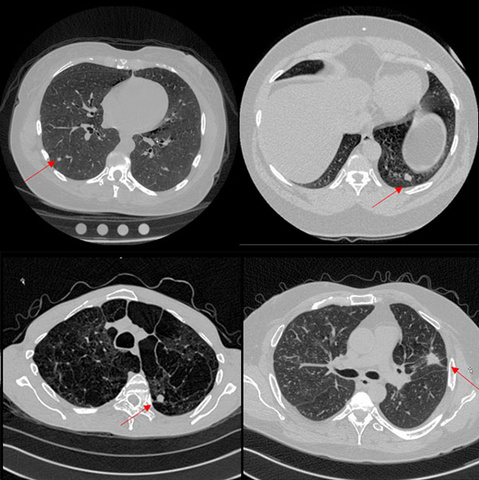

The Radiology Core Lab will provide a comprehensive set of quantitative imaging services for oncologic clinical trials, radiologic expertise for other image-based protocols including image-guided tissue biopsies and directed therapies. They will work closely with staff from Holden Comprehensive Cancer Center in the design of standard RECIST or other FDA-approved presentations of precise tumor measurements using annotated images, complete with an auditable, secure patient report. All radiological data for their clinical trials will be protected within their database management system. Benefits of the Radiology Core Lab include improved turnaround time and accessibility for study sponsors, decreased discordant interpretation rates, and collaborative interdepartmental research opportunities.

“The Department of Radiology will work in close partnership with principal Investigators of clinical trials at UI Hospitals & Clinics to provide accurate, reproducible, and timely quantifiable imaging biomarker assessments for CT, MRI, PET/CT, and US studies,” says Jinha Park, MD, PhD. “We hope to provide these services from board-certified diagnostic radiologists who do this every day and will improve the overall clinical trials experience for our physicians, nurses, clinical trials staff, and patients.”